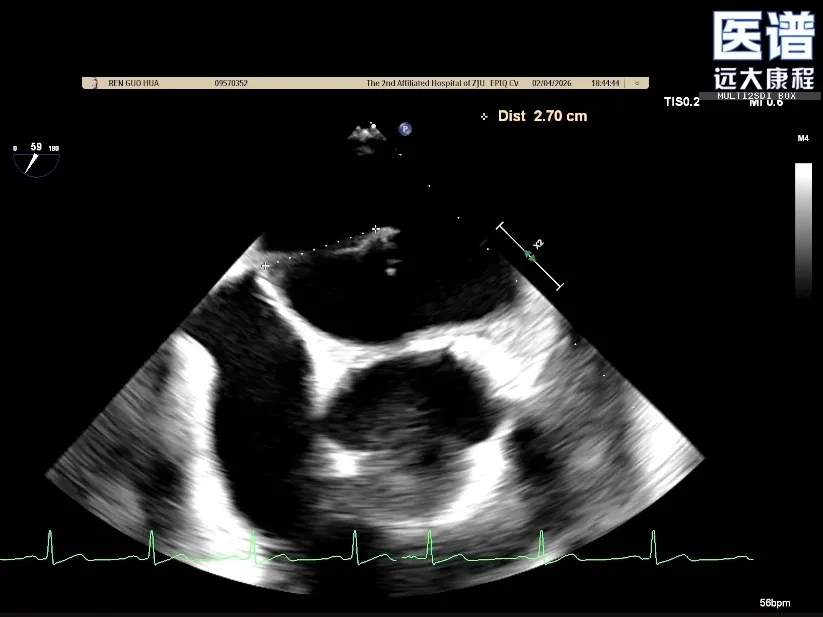

TEE-3D

重度DMR,LVEF 61%,LVIDd 5.62cm,LVIDs 3.27cm,VCW 0.72cm,EROA=0.47cm2;RV=83ml,PG mean 3mmHg,PASP 51mmHg。

病变位置为:A1邻近交界处脱垂;宽度/高度:1.08cm/0.29cm;A1/P1瓣叶长度:1.38cm/1.17cm;前后径(AP直径):3.56cm;二尖瓣口面积:4.39cm2